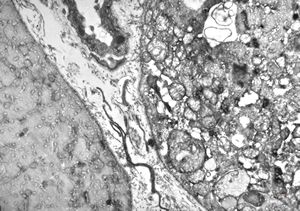

M,56y. | amyloidosis - tendon